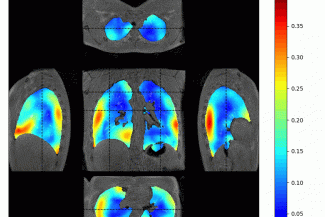

The COVID years were a wake-up call for the community, showing how important it is to diagnose lung diseases and monitor treatments safely and affordably. Today, lung diagnosis still relies mainly on X-ray–based methods, which are not ideal, especially for repeated scans or for use in children.

The Chest MRI Advanced School — organised by the European consortium V|LF-Spiro3D funded by the European Innovation Council and Innovate UK, with support from the University of Aberdeen — will bring together international experts and attendees to learn about the basics of lung anatomy, physiology, and function through the current diagnostic tools and the latest research in high- and low- field MRI. The event will offer a chance to engage with academics, NHS consultants, industry partners, anthropologists, radiographers, and patients to identify unmet needs and decide on the best path forward to improve safe lung diagnosis using MRI technologies.